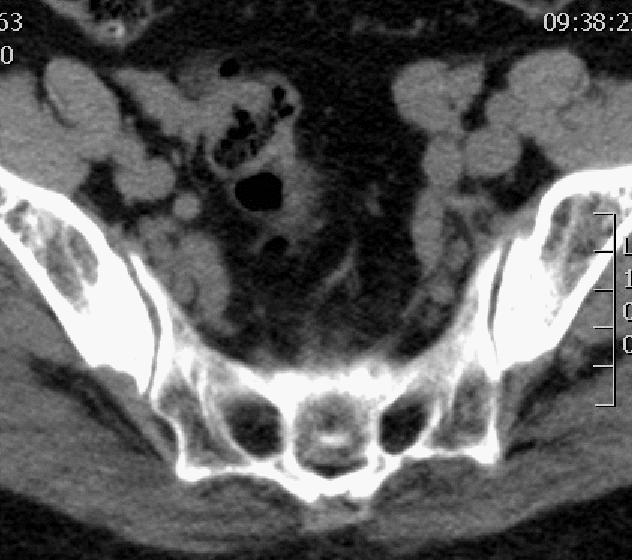

CT平扫

如图所示,红色箭头可见骶管及双侧骶孔扩张,内见哑铃型软组织密度影,绿色箭头所示骶骨后缘骨质受侵呈骨质破坏。